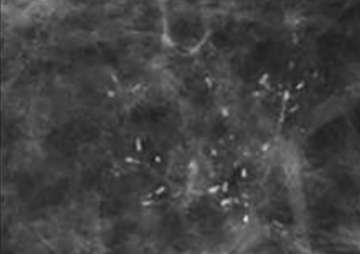

![]() Fine linear or fine linear branching: thin, linear and usually discontinuous calcifications which represent calcified necrotic debris within a duct compromised by carcinoma. When these calcifications are new and present in a segmental distribution, they are considered a BIRADS 5 category finding.